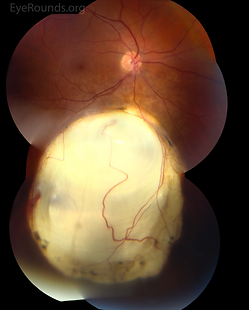

Chorioretinal Coloboma

Caused by the failure of the choroidal fissure to close on day 44, leading to the failed formation of ocular tissue. Whilst it affects the iris, lens, choroid, retina and optic nerve, chorioretinal coloboma affects only the choroid and retina, though can be associated with other colobomas.